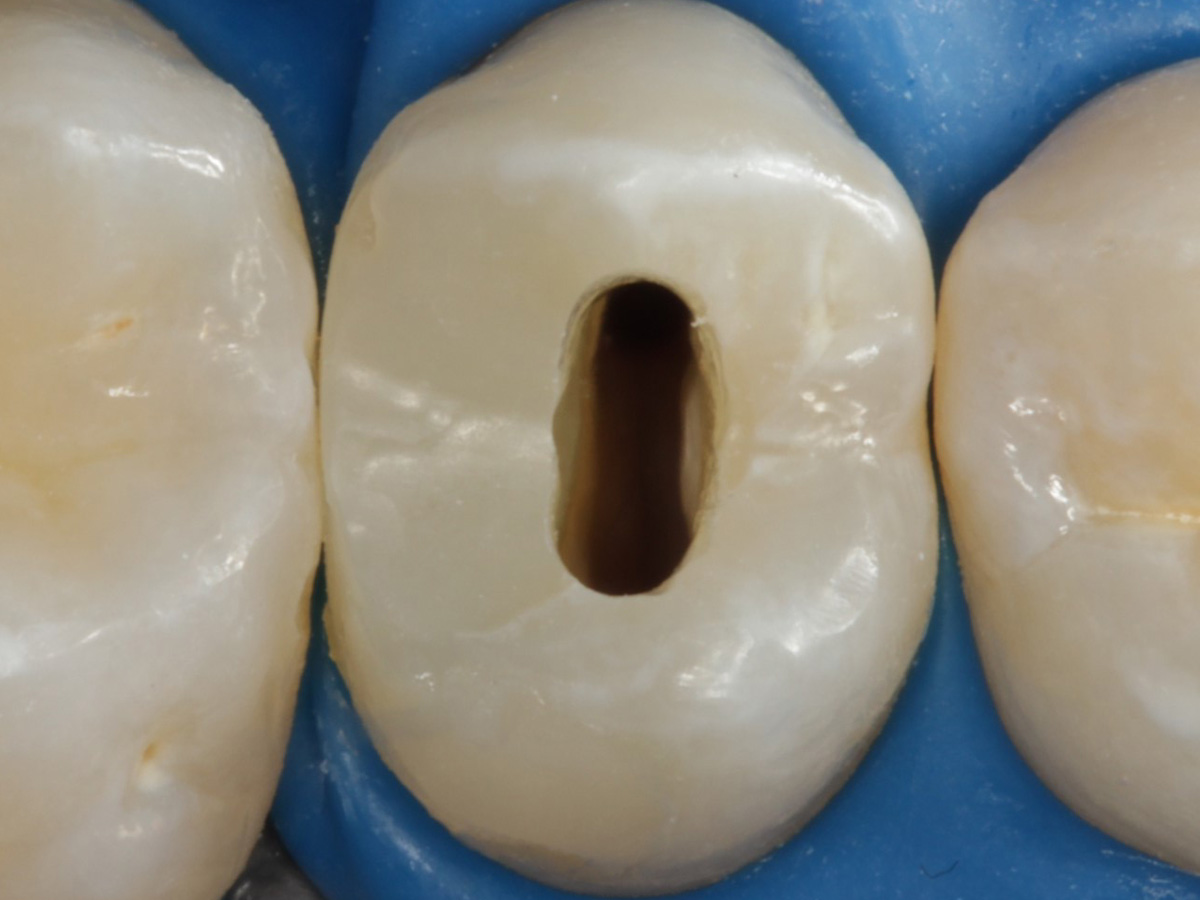

Abbildung 2

Intakte Kaufläche